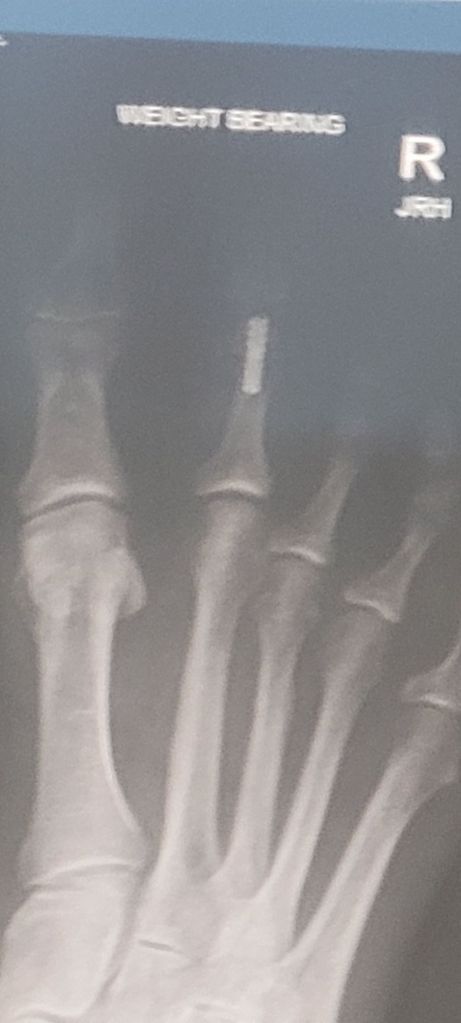

She inserted an artificial joint to straighten it out. I can just move the top. But that’s better than it was before.